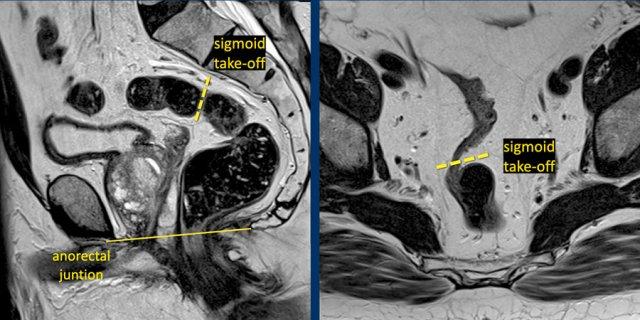

Điểm xuất phát của đại tràng sigmoid

Điểm xuất phát sigmoid (STO) như một mốc giải phẫu đã được thiết lập vào năm 2019 bởi một hội đồng đồng thuận quốc tế như là mốc hình ảnh ưu tiên để phân biệt trực tràng với đại tràng sigma(ref).

Định nghĩa này đã được ESGAR và các hướng dẫn của Hà Lan áp dụng.

Xác định Điểm Xuất Phát Sigmoid trên MRI

Đoạn xuất phát của sigmoid (STO) được nhận diện rõ nhất trên:

- Phim MRI mặt phẳng đứng dọc: Điểm mà tại đó đại tràng sigma chạy ngang ra xa xương cùng

- MRI trục: Điểm nơi đại tràng sigma nhô ra phía bụng (xem Hình)

Trong khi các biến thể giải phẫu hoặc góc độ của chuỗi hình ảnh đôi khi có thể gây khó khăn cho việc nhận diện, STO vẫn là một mốc giải phẫu trực quan và đáng tin cậy.

Các khối u có bờ dưới nằm gần với STO (phía trên chỗ nối đại tràng sigma-trực tràng) được phân loại là u đại tràng sigma.

Đo Chiều Cao Khối U

Chỗ nối hậu môn-trực tràng(mốc giải phẫu được sử dụng phổ biến nhất):

- Xác định ranh giới chuyển tiếp giữa ống hậu môn và trực tràng đoạn xa.

- Nằm ở góc hậu môn-trực tràng, được tạo thành bởi sự co cơ mu-trực tràng.

- Trên MRI mặt phẳng đứng dọc, thường được căn chỉnh với một đường tưởng tượng nối giữa bờ dưới của xương cùng và xương mu.